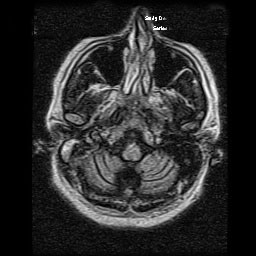

Spinocerebellar ataxias are a heterogeneous group of neurodegenerative diseases. There are more than 40 subtypes described so far, being spinocerebellar ataxia type 5 (SCA5) a rare autosomal-dominant ataxia with pure cerebellum involvement.  The gene responsible is the non-erythrocyte beta 2 spectrin gene (SPTBN2), encoding β-III spectrin, highly expressed in Purkinje cells. Onset is usually before 30 years, although it ranges from infancy to 70 years. The main clinical manifestations are limb and gait ataxia (> 90%); however, some patients also show trunk ataxia, sensory deficits, abnormal eye movements, dysarthria, and hyperactive deep tendon reflexes (25–90%).